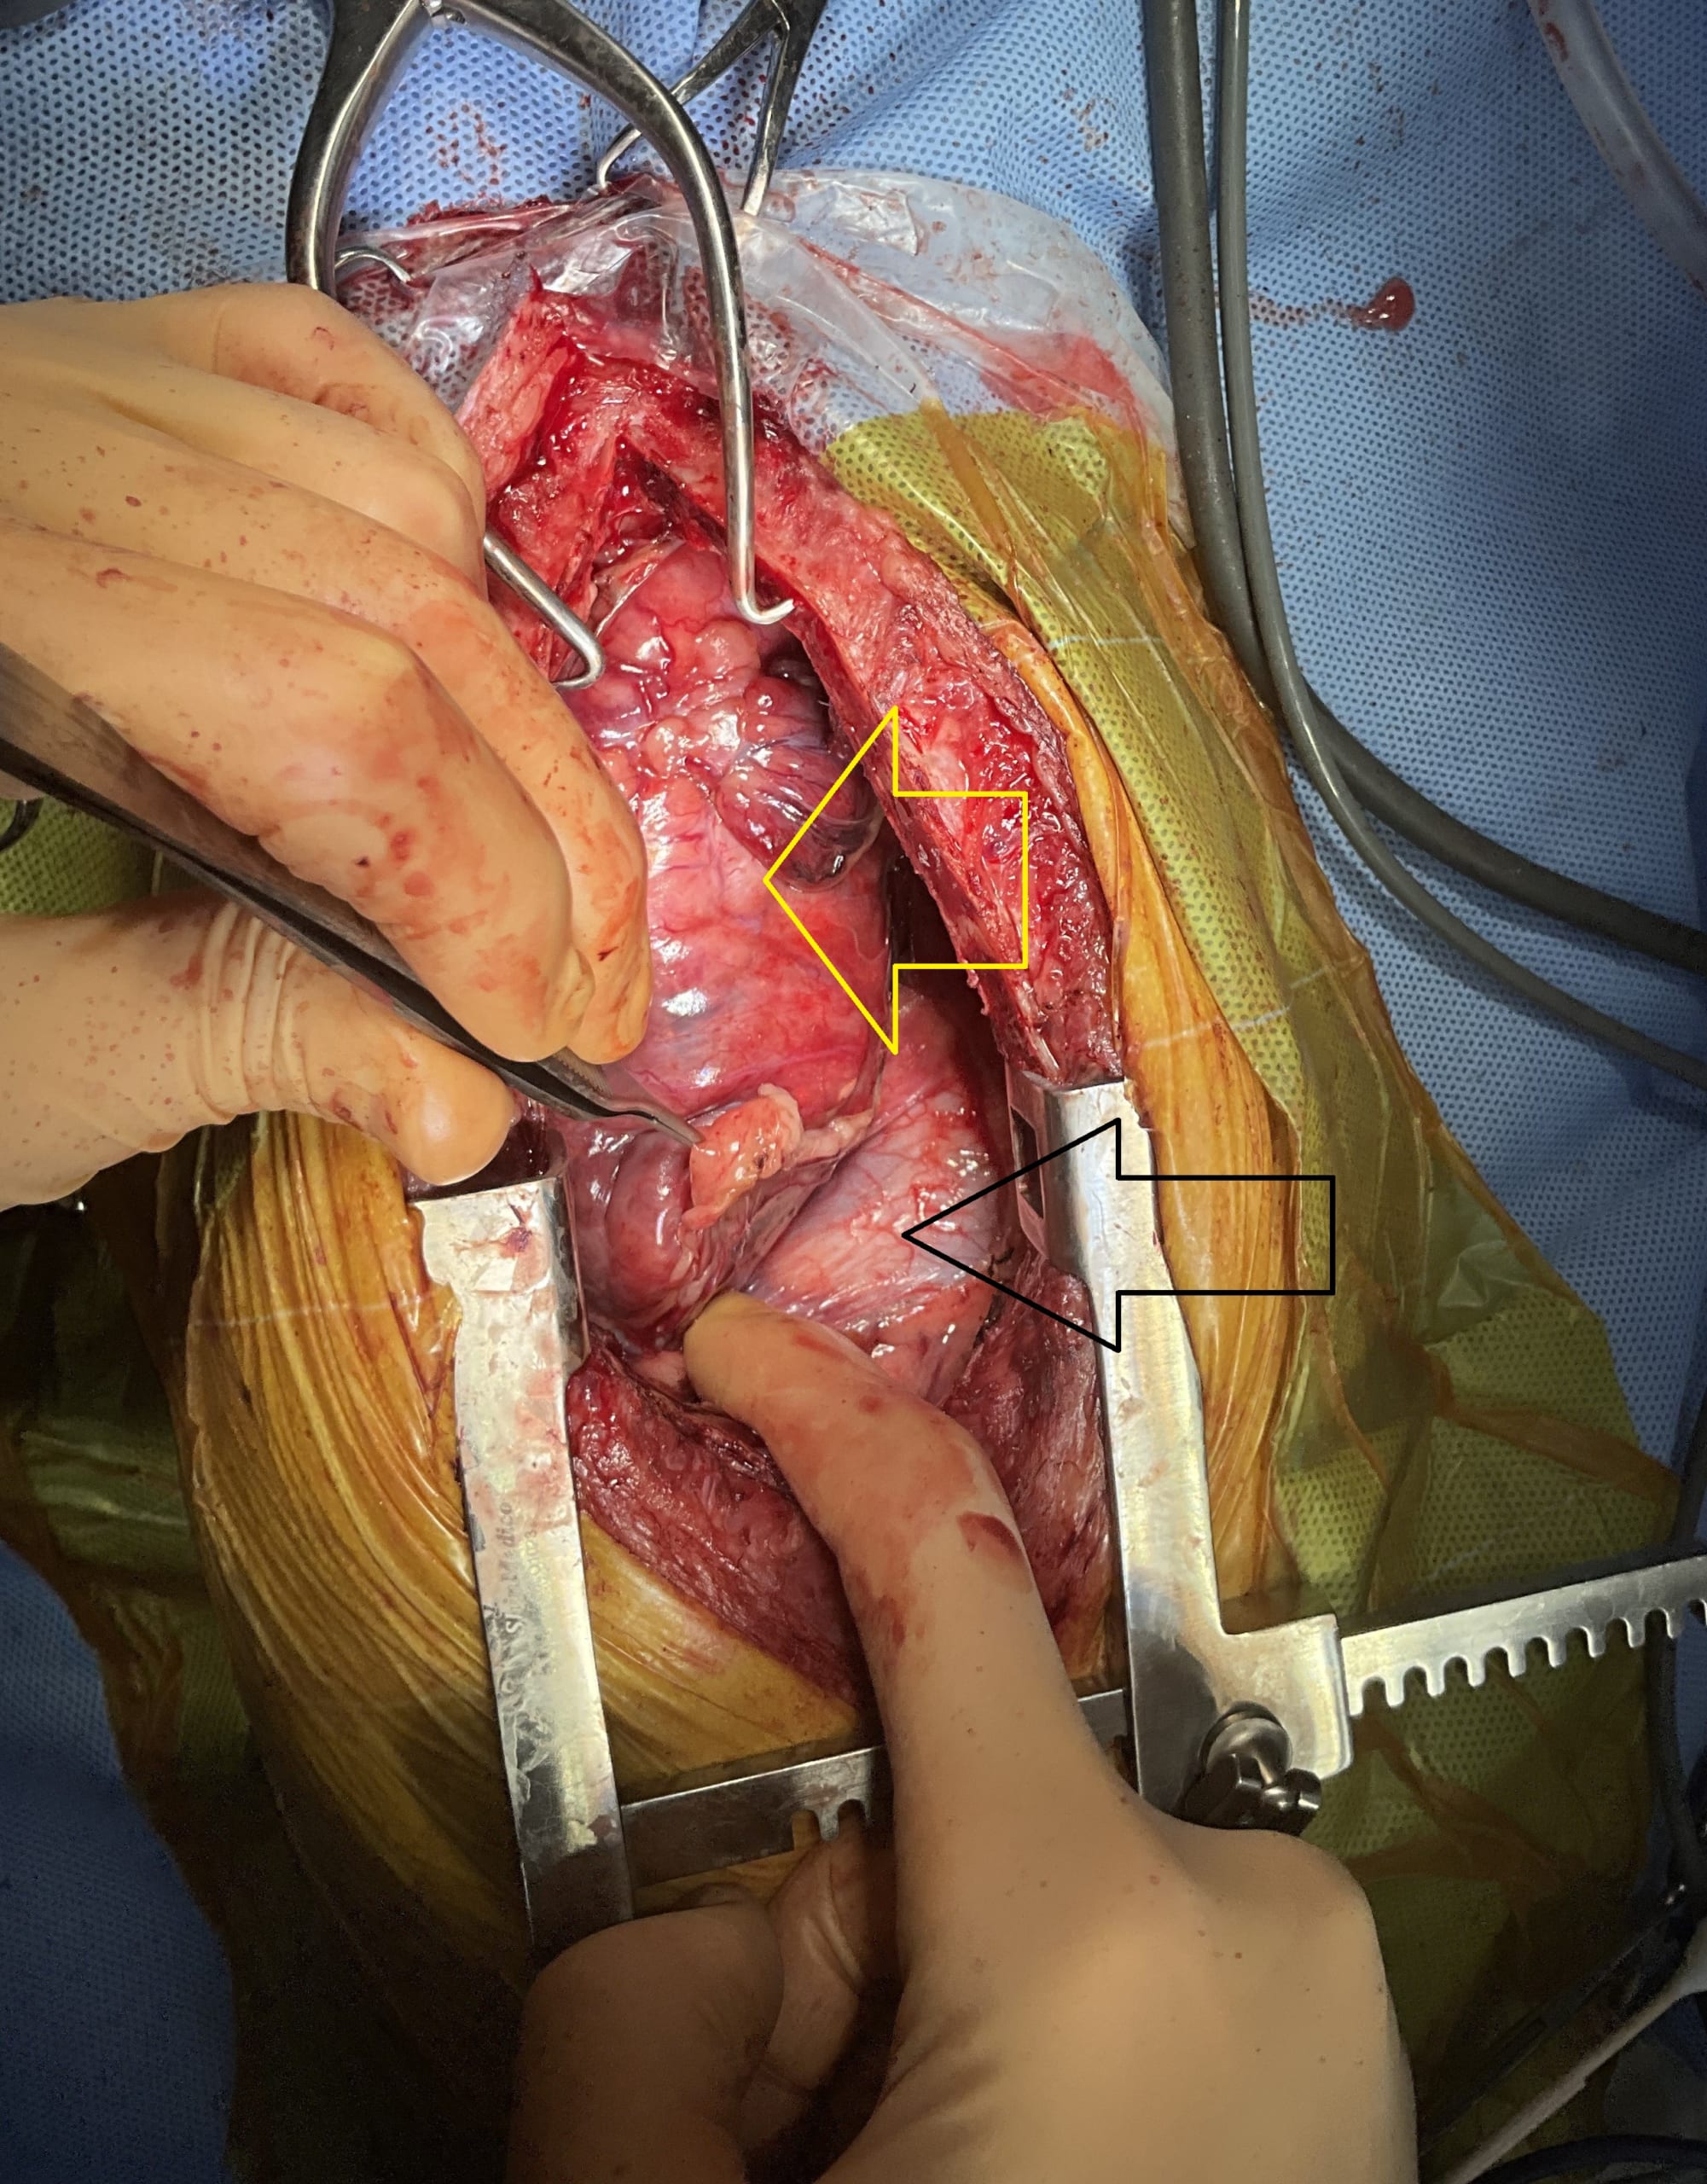

腫瘤(黄矢印)は心臓(黒矢印)にも癒着しており、心膜ごと切除する必要がありました。

また、前大静脈への癒着が認められたため、慎重に剥離操作を行いました。

しばらくすると、圧迫されていた肺(黒矢印)が徐々に膨らみ、呼吸の改善が期待できる状態となりました。